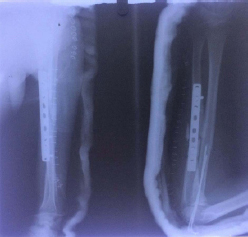

Surgery was planned. Open reduction and internal fixation of ulna was done with 9 hole LC-DCP (Limited Contact- Dynamic Compression Plate) and autologous bone grafting. Radial head did not reduce even after fixation of ulna so by using a different incision (Kocher’s approach) it was exposed. The radial head was not deformed and thick scar tissue filled the radiocapitellar space. After excision of scar tissue the radial head reduced. After reduction, on extension radial head was subluxating so two radio-capitellar Kirschner wires were placed to maintain the radial head reduction. Above elbow slab was given with forearm in 90 degree flexion and full supination [Table/Fig-2].

Postoperative x-rays showing radiocapitellar K wires and fixation of ulna.